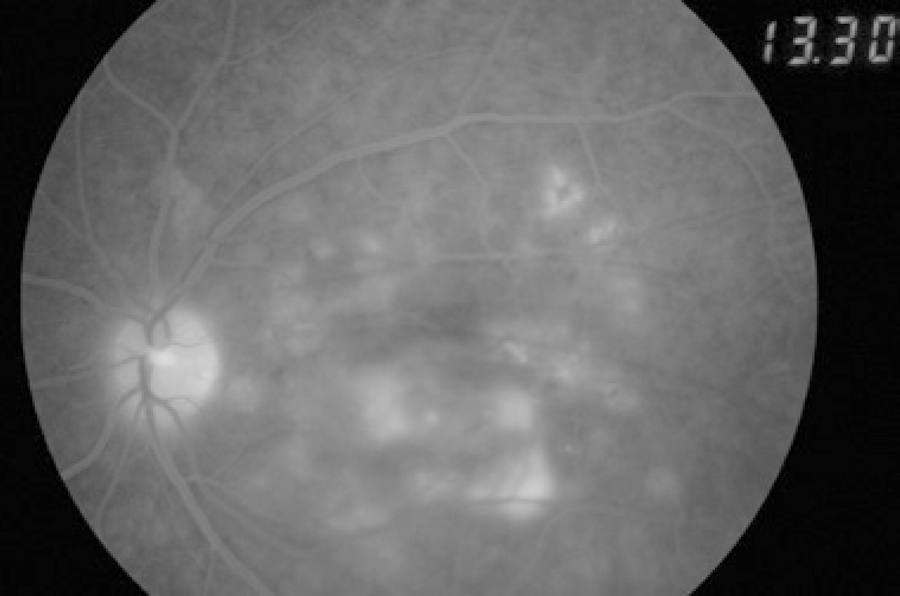

On fluorescein angiography, we found disc staining and multiple early pinpoint retinal pigment epithelial leaks (Figure 3).